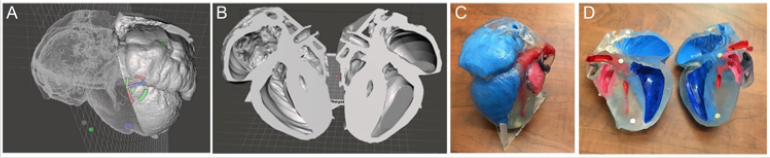

3D Printing

The final step in the process is 3D printing. Once a file is sufficiently prepared in Meshmixer and accuracy is ensured, it can be sent to 3D printer for production. The resultant model should be the exact same as what is viewable on the screen and can be used to better understand the phenotype of a given genetic model. This process generally takes 16-24 hours to complete. We utilized a single- color resin printer that utilizes SLA technology to solidify resin into the print. The models were enlarged to satisfactory dimension to visualize the details and were then printed in transparent resin which was then painted to further highlight the anatomic details. Upon completing several segmentations, mouse heart models were printed depicting hypoplastic left heart syndrome (HLHS) (Figure 7). These files were also kept in database to use for future phenotyping of deformities. These saved files and printed models provided further insight into the phenotype of each deformity present in the genetic mouse models. Before this method was developed, specifically for ECM scans, there was no way to create a model that would accurately depict deformities in three dimensions. With this new method, it is now possible to go from an image stack to a 3D model that accurately depicts phenotype, providing further insight into deformities shown in genetic mouse models.

Figure 7: 3D printing of mutant mouse heart from ECM source files with the hypoplastic left heart syndrome (HLHS) (A,B) Completed 3D processed digital model of a HLHS heart; (C, D) photographs of the 3D physical model of the HLHS heart. Red: left heart; blue: right heart.